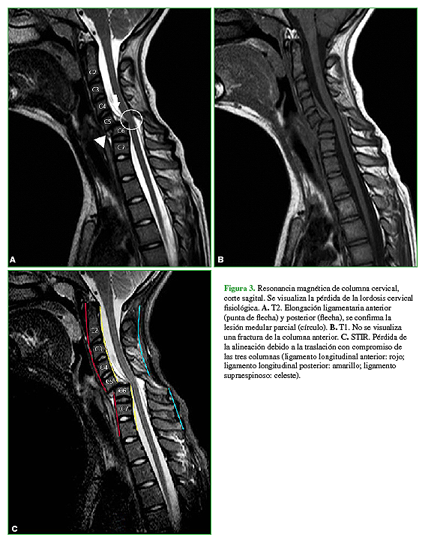

La resonancia magnética de columna cervical (Figura 3) incluye imágenes en el plano sagital ponderadas en T2, T1 y STIR, donde se continúa viendo la pérdida de la lordosis cervical fisiológica, elongación ligamentaria anterior y posterior, y se confirma la lesión medular parcial.